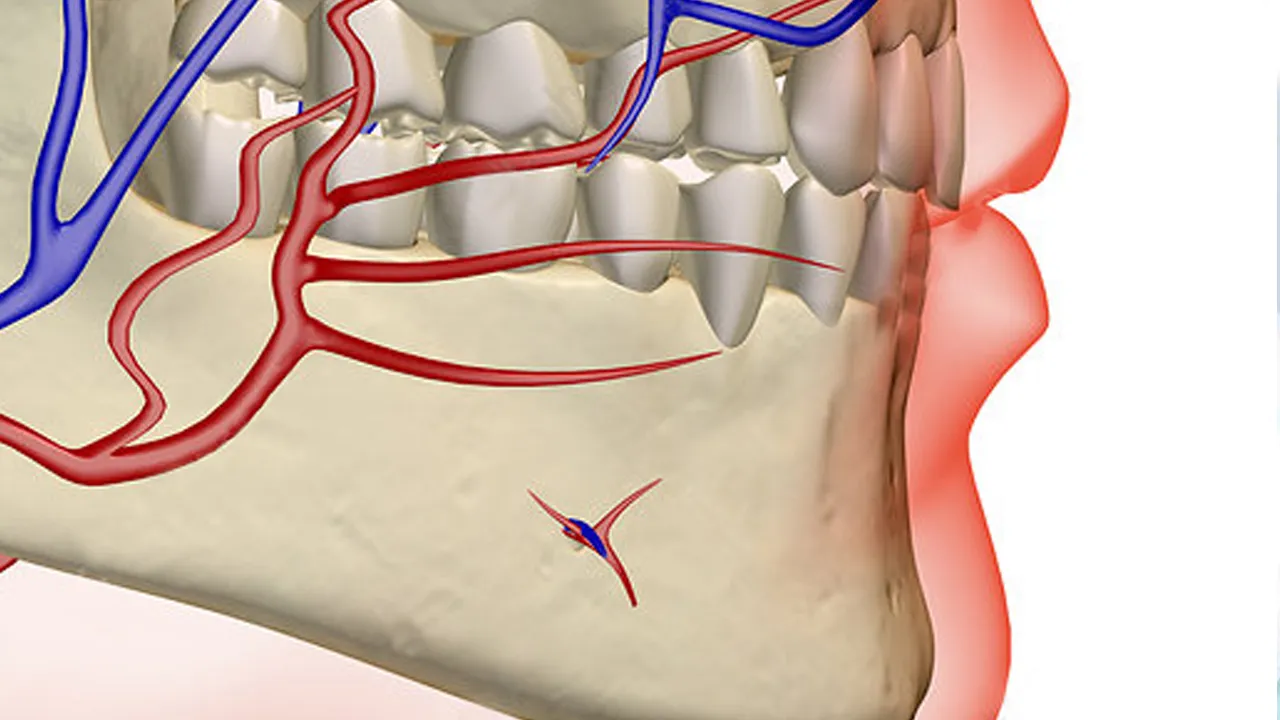

Dental implants are a simple and easy way to deal with oral problems. Generally, they have a very high success rate, but since they also come under the spectrum of medical procedures, they may have a few medical side effects. Side effects like discomfort, allergic reactions, nerve damage, and many more are commonly observed by the patients. This is why having dental implants from a verified and trusted dentist and regular checkups is highly advised.

Dental implants involve nerves in our teeth, so it is sometimes possible for people going through dental implants to suffer from nerve damage. Nerve damage can often result in a tingling sensation and numbness. Although the chances are very low as all the experts take proper measures to avoid this, visiting an individual you trust is highly advised to avoid such issues.

Having a risk of infections

As dental implants are also a medical procedure, it always has the potential for bacterial infections. Even after the cleaning and hygiene measures are taken, the patient’s mouth is opened for a prolonged period, which can lead to bacterial infections, and this can only be avoided with continuous cleaning and monitoring.